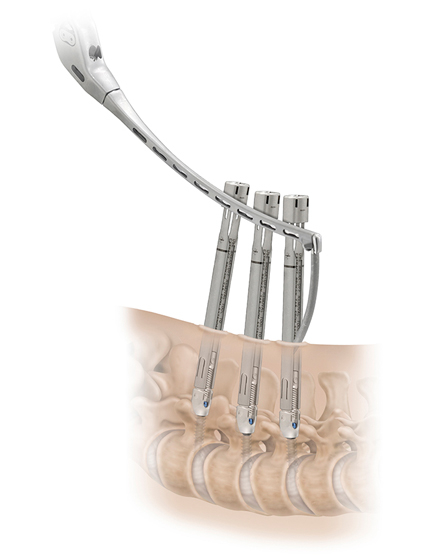

低侵襲脊椎側方固定術 XLIF (エックスリフ)、OLIF(オーリフ)

適応となる疾患:腰椎椎間板ヘルニア、腰部脊柱管狭窄症、腰椎変性すべり症、腰椎変性側弯症など

日本では2013年から承認されている低侵襲な脊椎側方固定術です。この手術は、トレーニングを受けた医師だけが実施できるため、全国でも限られた医療機関でのみ受けられます。当センターの日方医師は資格を有しているため実施可能です。この手術の最大の利点は脊髄神経を直接触らないで神経を圧迫から解除することにあります。側腹部に約5cmの皮膚切開により、下図のように神経機能を電気モニタリングで随時確認し重要な神経を避けながら椎間板内に人工骨を移植します。その後、腰部から固定術を行います。翌日から起立・歩行が許可され、入院期間は通常10~14日程度になります。